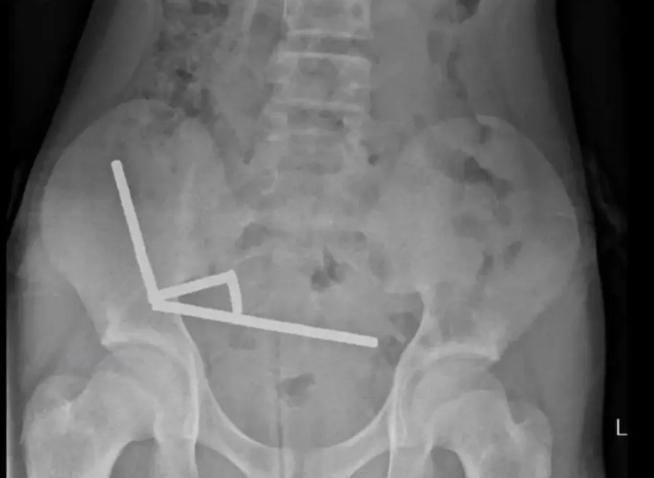

X光中顯示,這些小磁鐵在他腸子裡的不同部位中形成4條鏈子互相拉扯,並切斷了附近組織的血流,壓力更導致多處壞死。